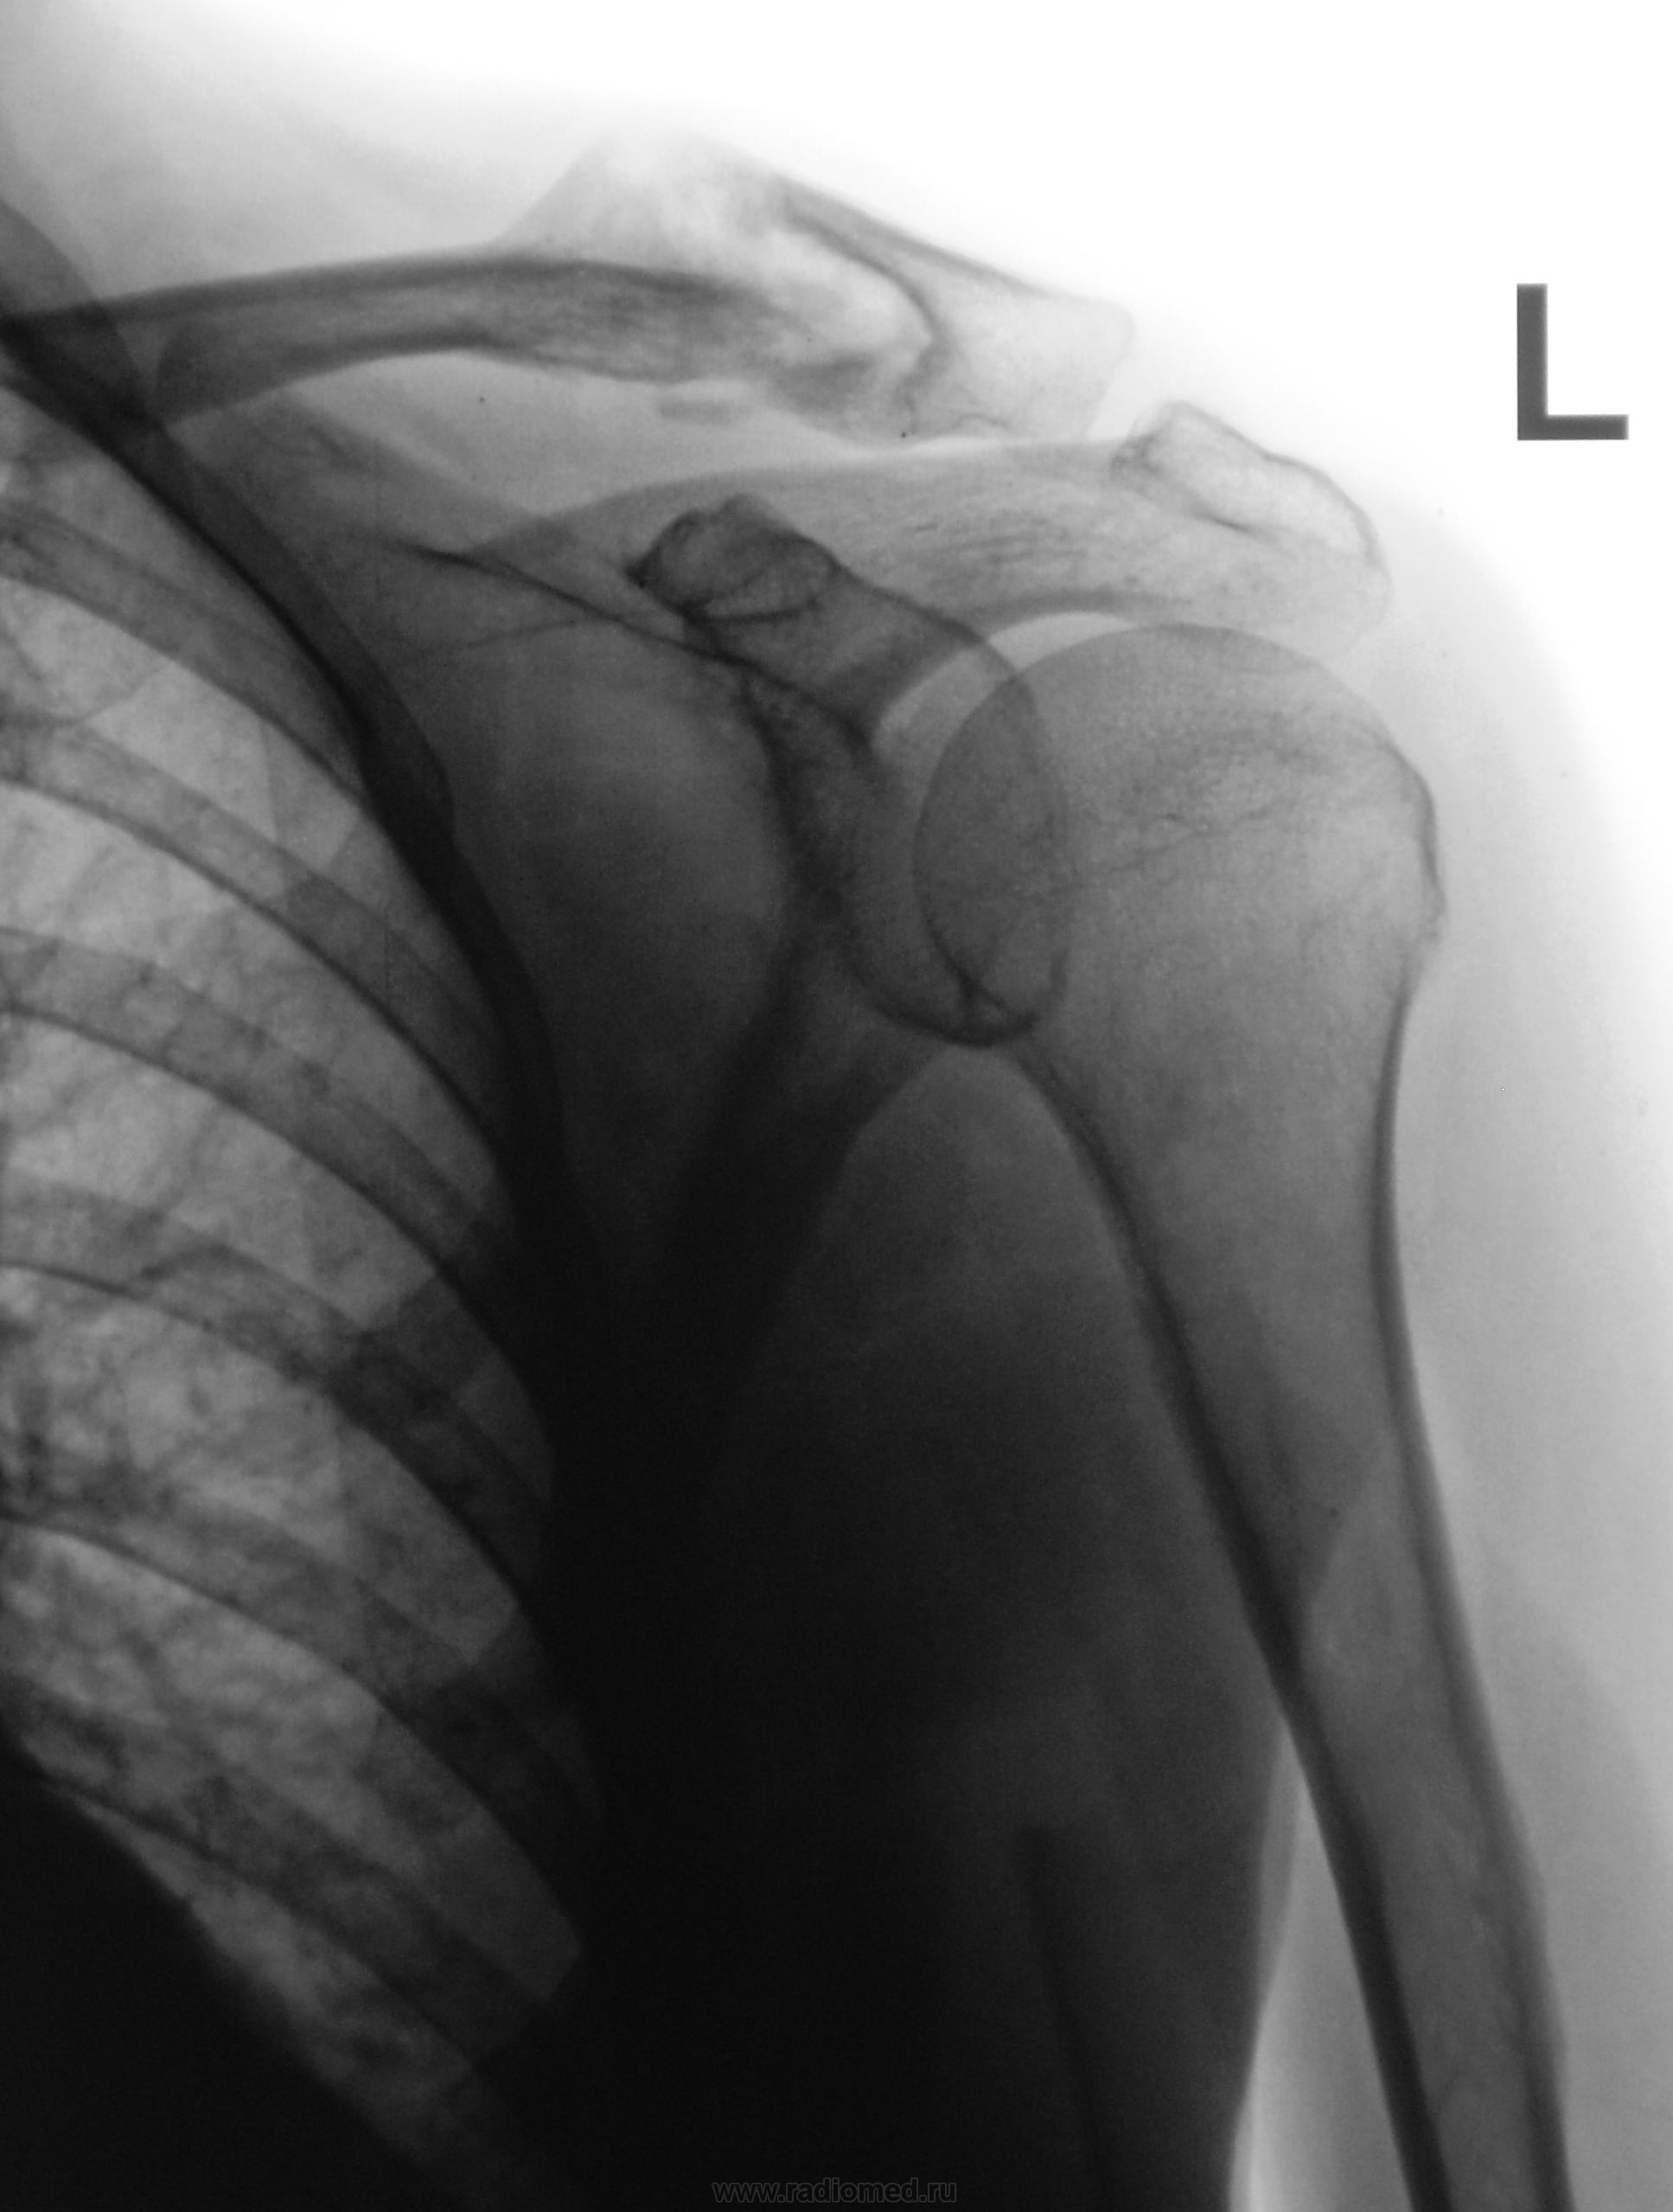

Пациент направлен на рентгенографию плечевого сустава хирургом с диагнозом экзостоз

Старый перелом, который сам решил срастись, причем с достаточно удовлетворительным стоянием отломком.

Для уточнения собрал бы анамнез у пациента : была ли травма ? давность начала заболевания ? Несколько необычная картинка...

Полагаю - аномалия с ложным суставом.

думаю патологический перелом нужно исключить.

Думается тугой ложный сустав акромиального конца ключицы (при наличиии анамнеза). Результаты при консервативном лечении лучше чем при оперативном (что нельзя сказать про Ро-картину-красота при оперативном лечении и не понятно что при консервативном).

Мне думается, что это образовался ложный сустав. Очень чёткая замыкательная пластинка.

Экзостоза нет, есть ложный сустав.

я бы это все назвала избыточная костная мозоль

Очень похоже, тоже склоняюсь к этому выводу, но, для подстраховки, я бы сделал снимок дав пациенту в руку что-то тяжелое.

доснять акром. конец  ключицы и  в другой проекции, попытать пациента насчёт травмы. Считаю, что здесь очень неплохо сросшийся перелом ( о ложном суставе и экзостозе я бы не думала).

А, пациент травмы и не отрицает, но считает, что травма была не значительной, и он (пациент) в ЛПУ не обратился.